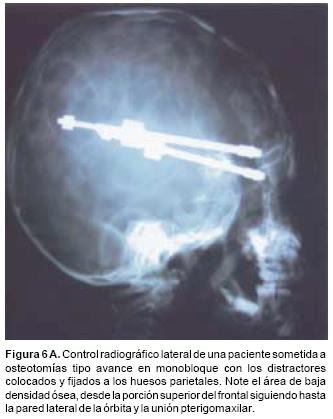

En todos los pacientes se logró el avance planificado de los segmentos óseos, al corregir la deformidad del hueso frontal, el exorbitismo y en la retrusión del tercio medio en los casos con avance en monobloque. Los avances mayores se obtuvieron en el hueso frontal y variaron entre 16 y 30 mm., mientras que los menores fueron los del hueso maxilar que fluctuaron entre 9 y 16 mm. (Cuadro I). Radiológicamente los controles postoperatorios tempranos mostraron inicialmente áreas de hipodensidad ósea, que al final del periodo de consolidación cambiaron a áreas de densidad ósea radiológica normal, lo que significa neoformación de hueso. Las áreas de hueso neoformadas que consolidaron en forma más rápida, son las ubicadas en las líneas de osteotomía de la unión pterigomaxilar, pared lateral de la órbita y unión frontoorbitaria. Las áreas que más tardaron en consolidar incluye la porción lateral y superior del hueso frontal.

También los controles radiológicos durante el proceso de distracción mostraron que no se produjo la creación de espacios muertos intracraneanos durante los avances. En todos los pacientes con sinostosis bicoronal el avance frontoorbitario produjo excelentes resultados estéticos dando una nueva forma a la región frontal y proyectando mejor el reborde supraorbitario. En los niños con enfermedad de Crouzon y síndrome de Apert, se corrigió en forma muy satisfactoria el exorbitismo al resolver las graves exposiciones corneales (Figuras 5 A, B, C, D, E, F, G, H), en los que se utilizó el avance simultáneo del tercio medio, este cambio óseo corrigió muy satisfactoriamente la retrusión del mismo, ampliando la vía aérea y resolviendo en muchos casos grandes problemas ventilatorios durante el sueño (Figuras 6 A, B, C, D, E, F). Los pacientes con plagiocefalia corrigieron significativamente la deformidad frontoorbitaria y los tejidos blandos suprayacentes se adaptaron a la nueva estructura ósea. La clásica órbita de arlequín de estos niños producida por la sinostosis del frontal con el esfenoides, inmediatamente se ve corregida en su forma y su configuración se hace muy similar con la órbita contralateral (Figura 7)(Fig. 7a, 7b, 7c, 7d, 7e, 7f, 7g) (Cuadro II).

Una vez que las estructuras óseas se han movilizado se procede a la inserción de los distractores óseos. Éstos son de diseño tipo sumergido y consisten en una barra metálica de titanio que en su extremo distal se le acoplan diferentes tipos de ganchos que se adaptan a los diferentes segmentos de las líneas de osteotomía, ya sea a nivel orbitomalar, orbitofrontal o al mismo hueso frontal. En su extremo proximal presenta una cuerda de tornillo con una longitud de 30 mm., ésta se inserta a una base metálica cuadrangular, la que tiene perforaciones a través de las cuales el distractor se fija con 3 o 4 tornillos al hueso parietal. Desde este punto el distractor emerge a través de la incisión coronal y desde este punto se activa en el sentido de las manecillas del reloj, a fin de realizar el avance óseo. Vale la pena mencionar que como durante la disección se respeta el músculo temporal, el distractor cuando se coloca, se hace a través del espesor del músculo en dirección al sitio donde se quiere adaptar a fin de que produzca la fuerza mecánica necesaria para avanzar los segmentos óseos.

De acuerdo al tipo de avance que se planee a cada paciente se puede utilizar un solo distractor (plagiocefalias), dos distractores (avances fronto–orbitarios) o incluso cuatro distractores (osteotomías tipo monobloque).